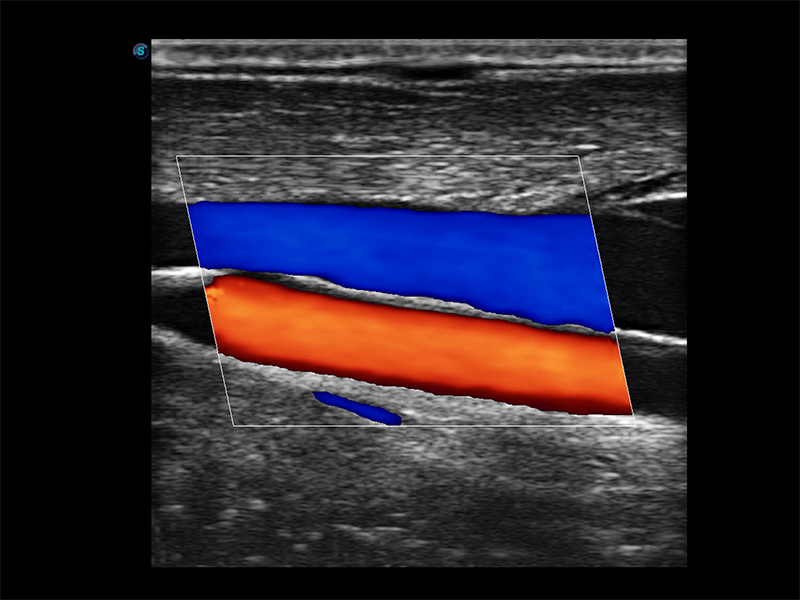

· Siêu âm Doppler năng lượng (PDI) / Siêu âm Doppler năng lượng định hướng (DPDI)

· Siêu âm Doppler màu (CFM)

· Chế độ đồng thời (Duplex)

· Chế độ đồng thời (Triplex)

· B / C hiển thị đồng thời (Dual Live)